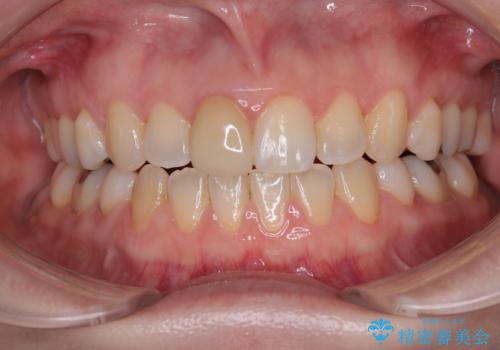

抜歯矯正で閉じにくかった口を閉じやすく改善

- 上の前歯の飛び出した感じを改善したいとのことで来院された患者様です。

上顎左右第一小臼歯2本、下顎左右第二小臼歯2本を抜歯し、ワイヤー装置にて口元を引っ込めるよう矯正治療を行うこととしました。

上下の前歯に隙間が空くほど上顎前歯が前に飛び出していましたが、抜歯矯正により上下前歯がぴったりと付くほど口元を引っ込めることができました。